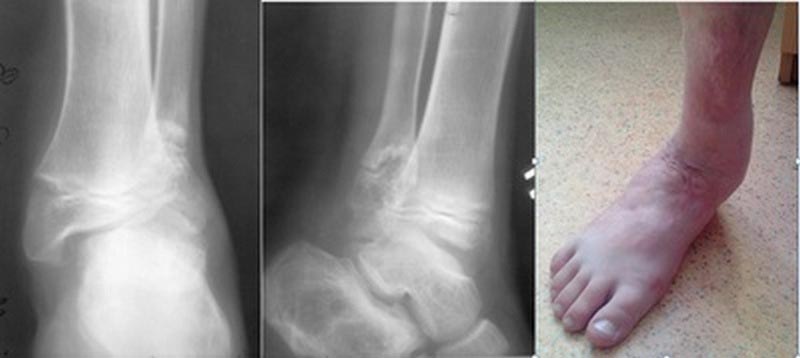

Посттравматическая деформация (нестабильность) голеностопного сустава у

ребёнка 13 лет.

6 лет после ДТП. Жалобы на сильную боль при ходьбе . Разрушена вилка

сустава, за счет деформации и укорочения наружной лодыжки . Поэтому

стопа уходит в вальгус . Артродез не вариант - ребенок растет .